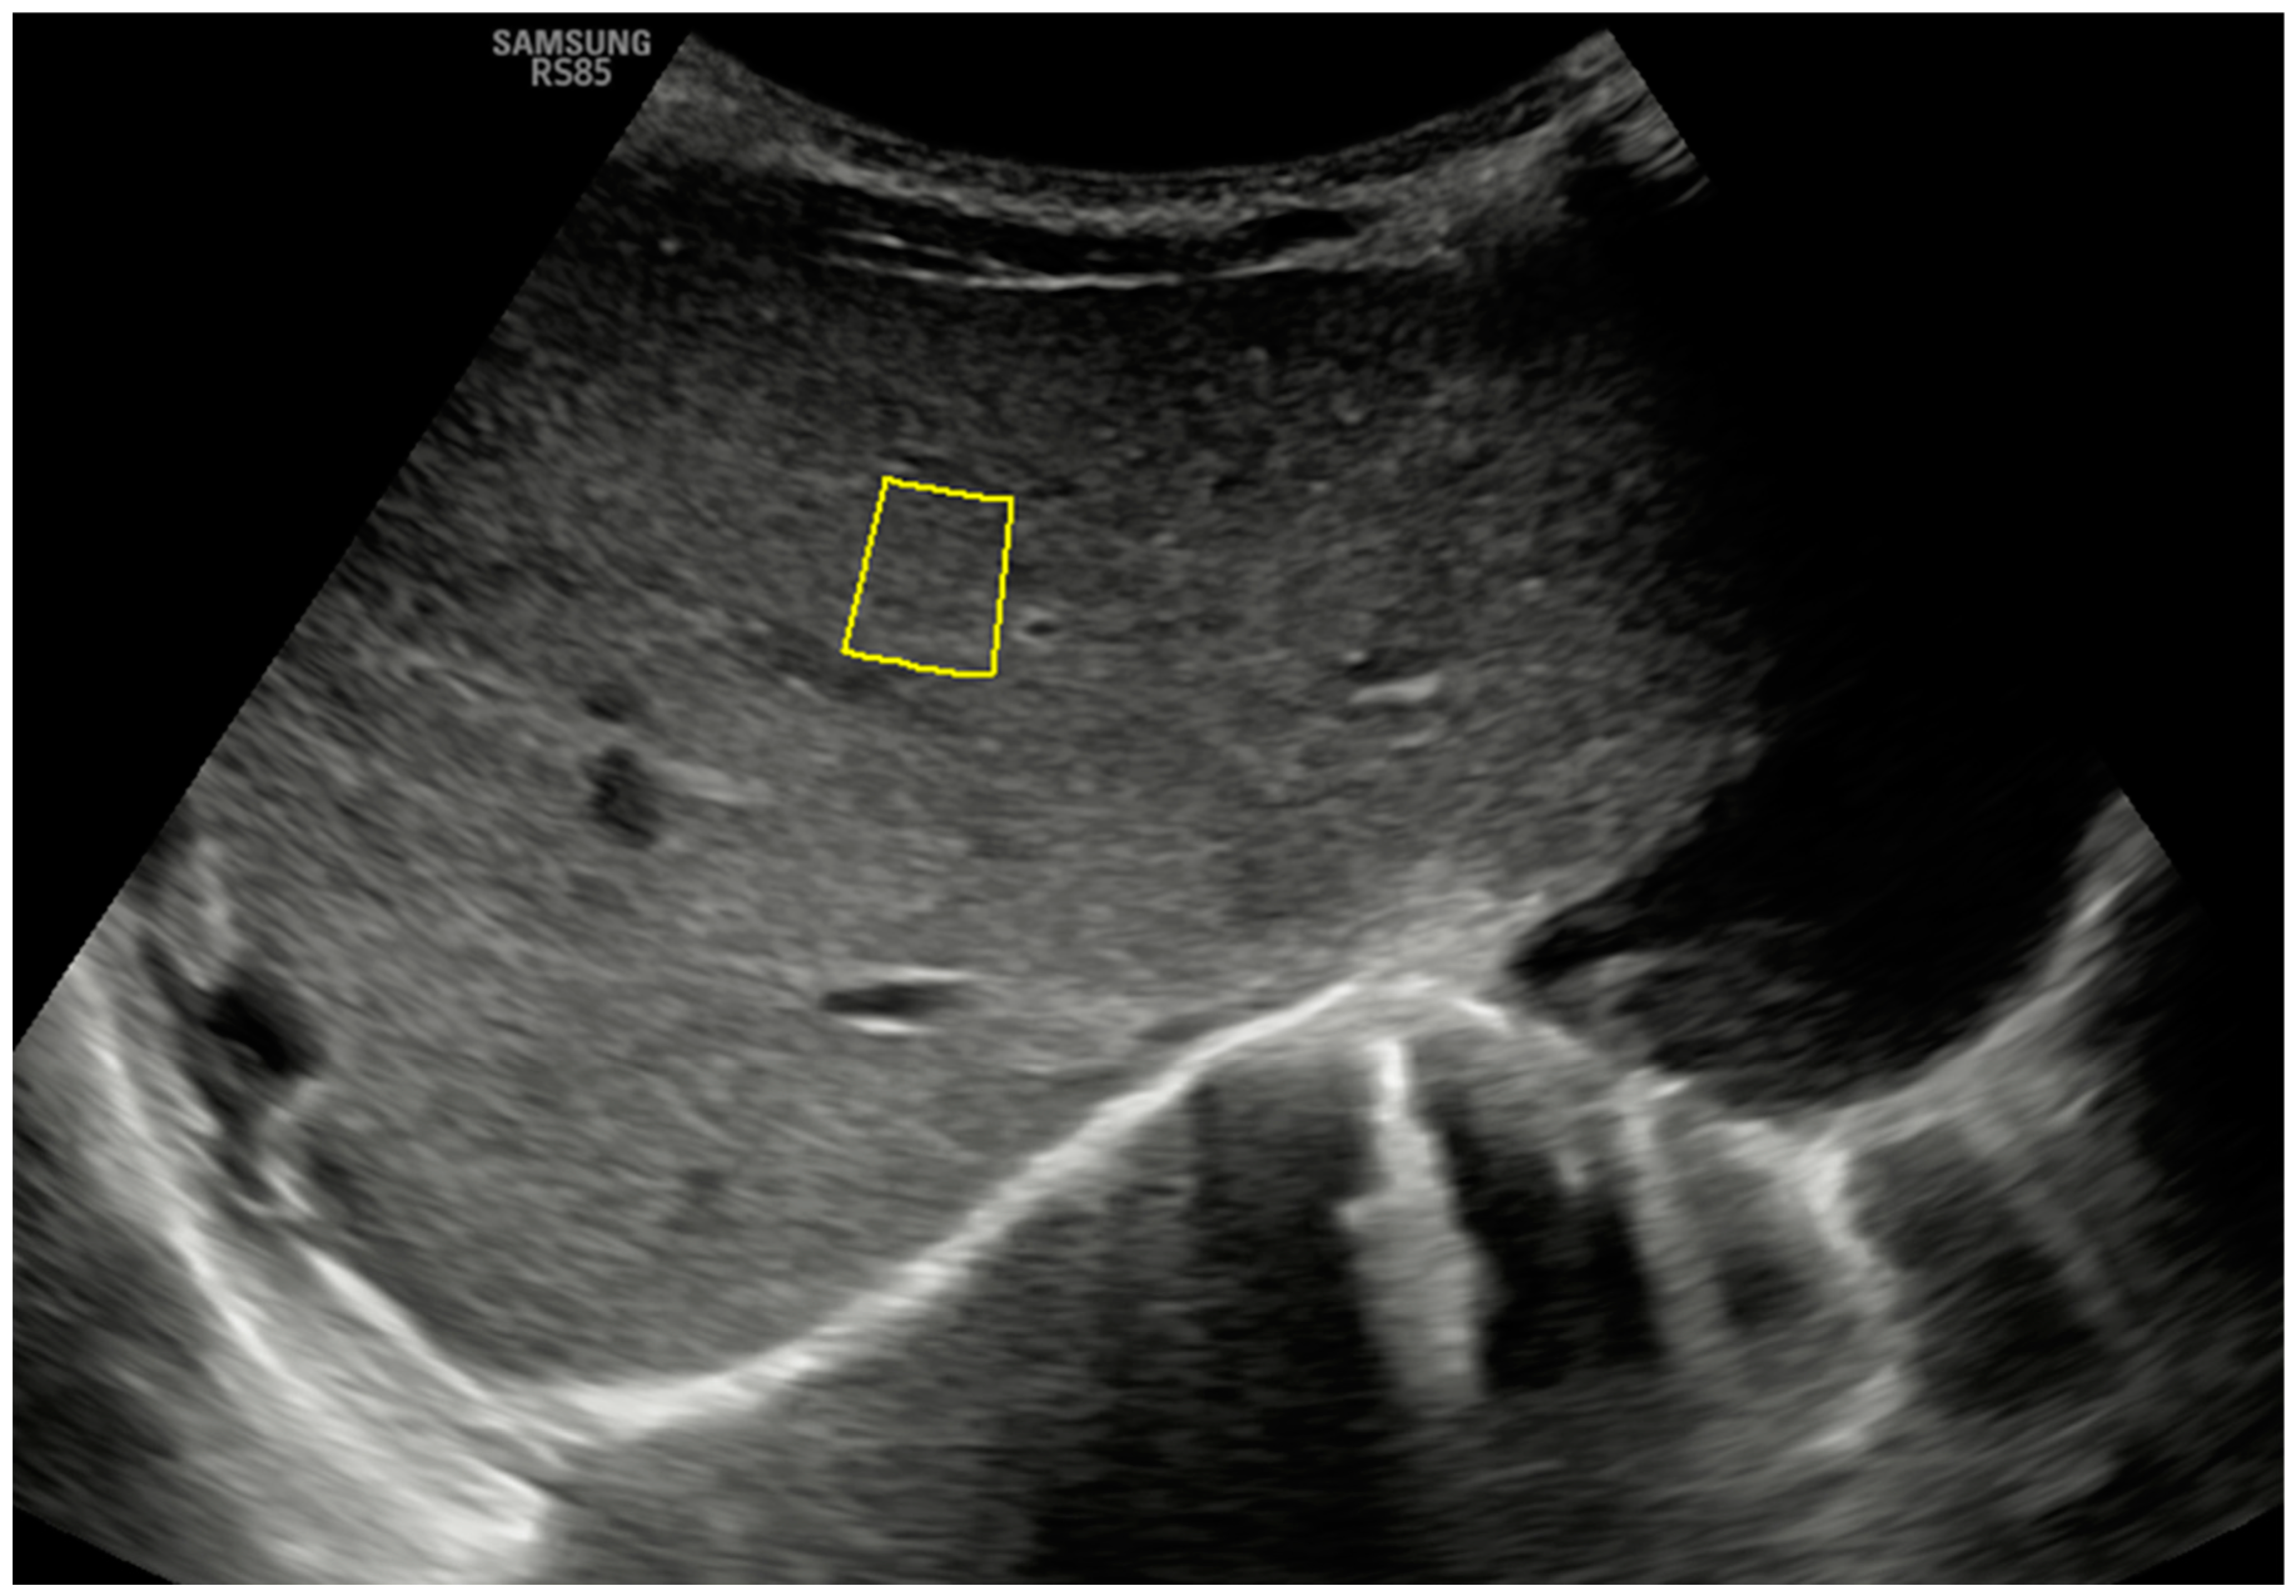

To perform these elastography procedures, both probes are placed transversely in a subcostal location along the right parasagittal midline, where segment IV of the liver can be visualized. Figure 1 shows the B-mode anatomical plane obtained using this approach, corresponding to an oblique axial plane just below the hepatic veins, and how the pSWE measurement is taken. The region of interest (ROI) should be positioned in the center of the ultrasound beam, within 1 cm of the liver capsule and up to 8 cm from the skin’s surface. ROIs are placed at different depths, and the measurement must have an internal quality factor (Reliability Measurement Index or RMI on our ultrasound machine) greater than 0.4 (range 0.0 to 1.0) to be considered adequate. It is desirable to obtain at least 10–15 adequate measurements so that the program will calculate the average obtained in kilopascals (kPa) and meters per second (m/s). The obtained average will only be considered representative if the interquartile range of the suitable measures obtained, divided by the median of this average, is less than 30% for the kPa parameter and below 20% for the m/s parameter (ideally below 20% and 10%, respectively) [2,3].

Figure 1.

A B-mode ultrasound image in the hepatic anatomical plane focuses on segment IV and shows the correct positioning of the ROI for pSWE with a convex probe. Note the quality measurement (on this device, RMI) of 0.7.